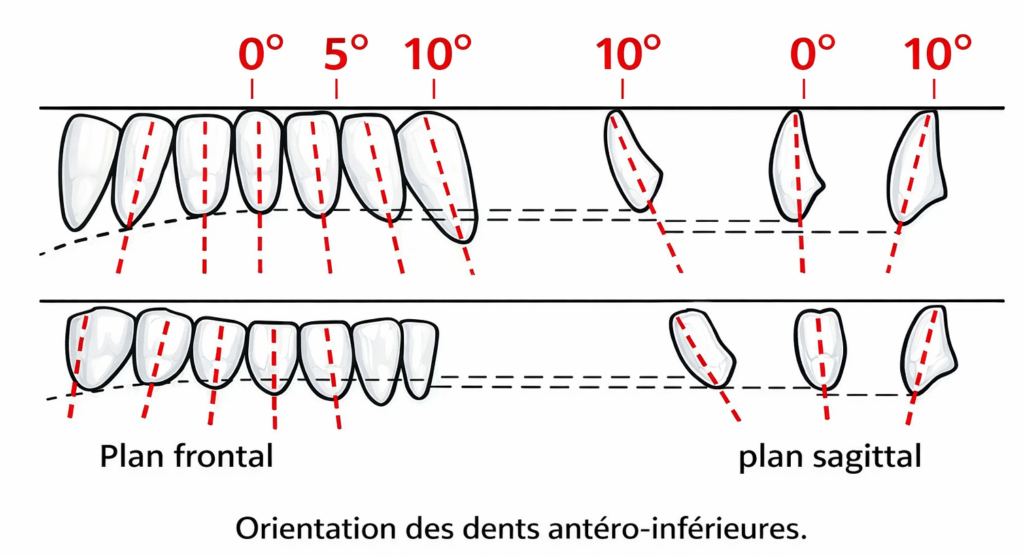

Orientation des dents antéro-inférieures

L’incisive centrale inférieure

Plan horizontal :

Sa position s’inscrit dans l’aire de sustentation d’Ackermann. Elle est montée sur le versant externe de la crête (talon de la dent placé de 1 à 2 mm en avant de la crête).

Plan frontal :

Son axe est perpendiculaire.

Plan sagittal :

Légère inclinaison linguo-vestibulaire de 10° qui ne doit pas aboutir à un contact avec la lèvre inférieure.

L’incisive latérale inférieure

Plan horizontal :

Sa position s’inscrit dans l’aire de sustentation.

Plan frontal :

Son axe est incliné de 5° par rapport à la verticale.

Plan sagittal :

Pas d’inclinaison.

La canine inférieure

Plan horizontal :

Sa position s’inscrit dans l’aire de sustentation dans le prolongement de l’incisive latérale.

Plan frontal :

Le grand axe est légèrement incliné dans le sens disto-mésial.

Plan sagittal :

Axe incliné de 10° dans le sens vestibulo-lingual.